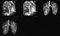

3D image of the tracheal bifurcation 3D image of the tracheal bifurcation CT of tracheal bifurcation Tracheal cancer 6. Examine the surfaces and hilum of the lung. Identify the lymph nodes involved in lymphatic drainage of the lungs. (Play movie; View images: N 196, 197, 198, 199, TG 4-13A, 4-13B, 4-15, 4-16, 4-17, 4-31)